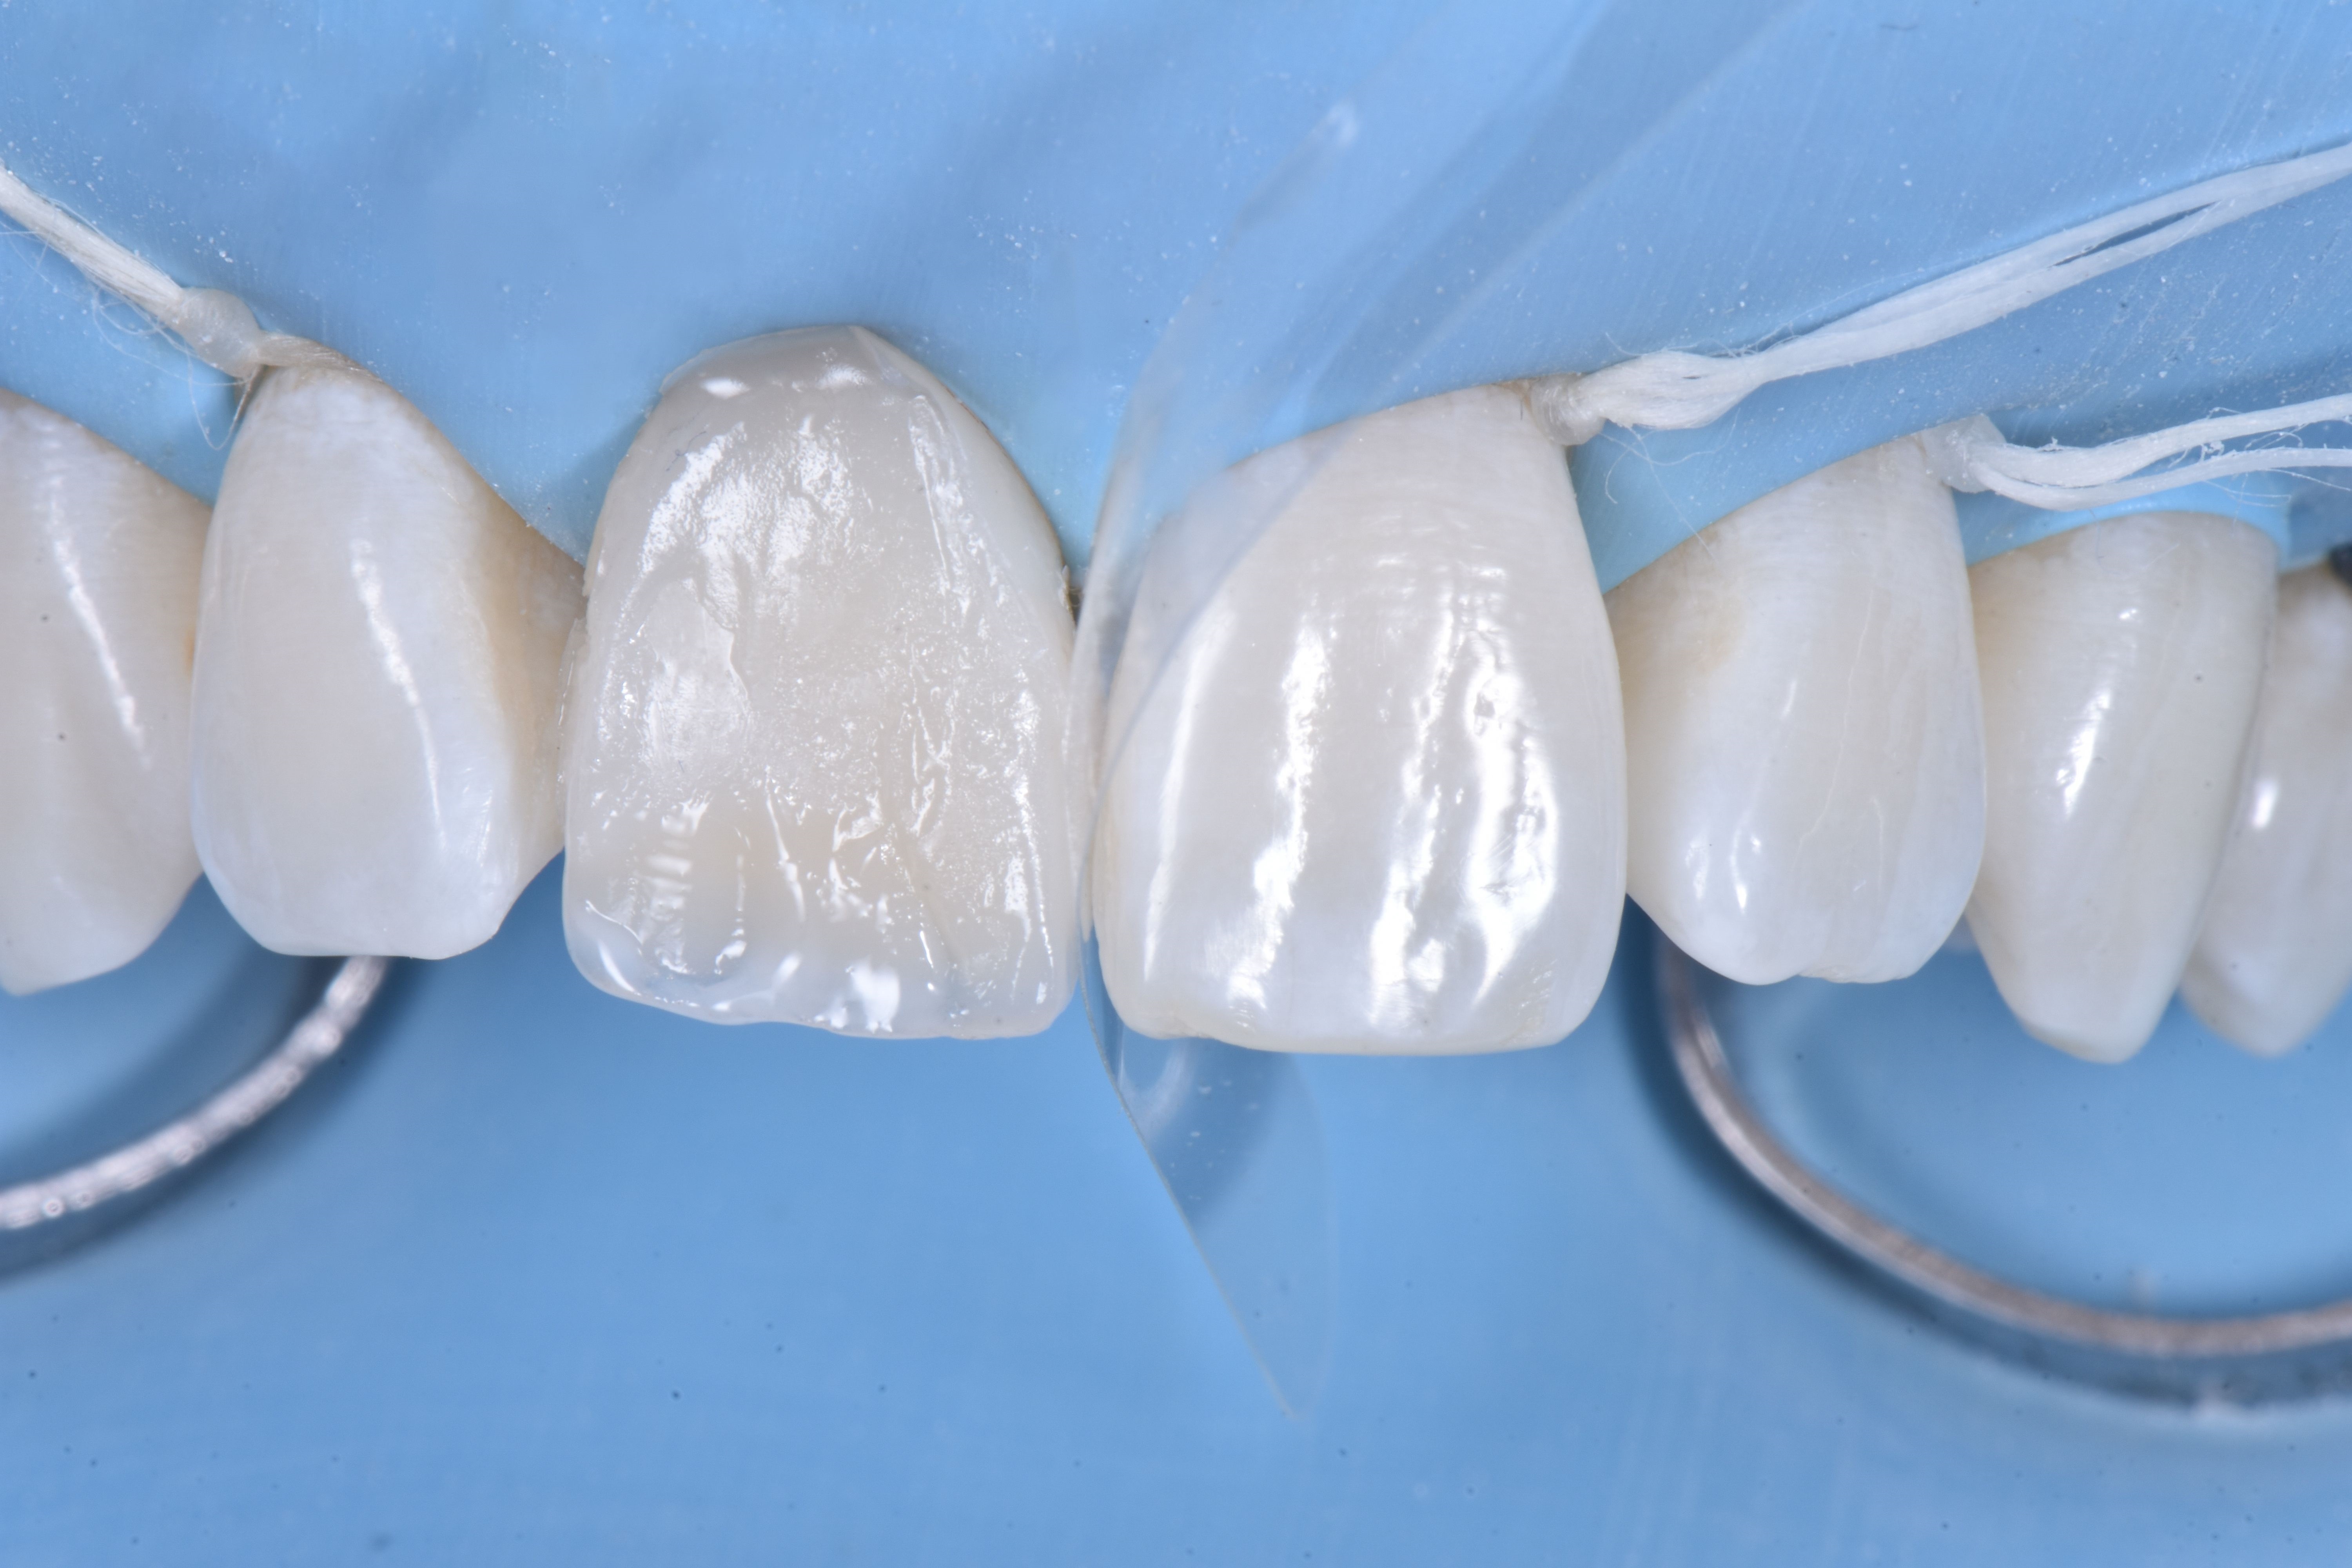

Następnie zrekonstruowano anatomię zębiny poprzez odtworzenie mamelonów przy użyciu opakerowego odcienia kompozytu do zębiny (ESTELITE SIGMA QUICK OA2 firmy TOKUYAMA DENTAL); odcień ten miał również zasadnicze znaczenie dla skorygowania odcienia przebarwionej korony (ryc. 9).